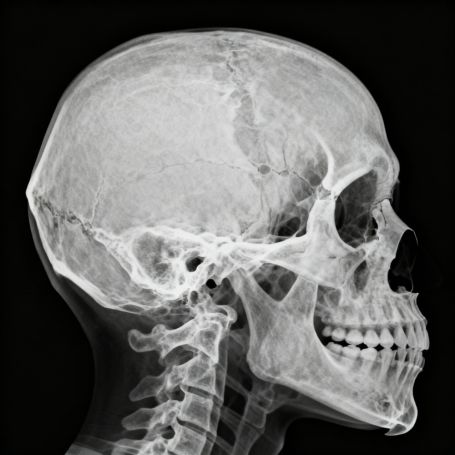

The X-Ray Skull – Townes View is a specialized radiographic technique designed to capture detailed images of the skull, particularly the occipital region and the foramen magnum. This view, also known as the AP axial skull view, helps radiologists visualize bone structures that are not clearly seen in standard X-rays. At Diagnopein, Karad, we use advanced digital X-ray machines to ensure high-quality, accurate images with minimal radiation exposure for patients.

Townes view X-ray scans are often recommended to assess skull fractures, cranial base injuries, and abnormalities in the occipital bone or petrous ridges. It provides a clear and diagnostic visualization of deep cranial areas that are crucial in trauma cases and neurological evaluations.

An X-Ray Skull – Townes View is vital for diagnosing several head and cranial conditions. It plays a crucial role in detecting fractures of the occipital bone, skull base injuries, and congenital bone abnormalities. The precise imaging helps in neurosurgical planning and evaluating chronic headaches or post-traumatic complications.

This imaging technique is preferred by doctors because it provides a perpendicular projection of the skull base, reducing distortion and allowing a better view of the structures lying near the foramen magnum. In emergency and trauma cases, the Townes view X-ray contributes to fast and accurate assessment, which supports prompt medical intervention.